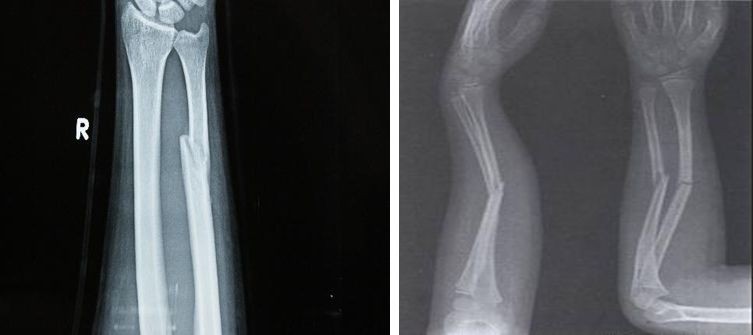

1、锁骨骨折

功能锻炼方法:

握拳、伸指、分指、腕屈伸、腕绕环、肘屈伸、前臂内外旋等主动练习,幅度尽量大,逐渐增加用力程度。

骨折后2周可增加捏小球,抗阻腕屈伸运动及被动或助力的肩外展、旋转运动等。

骨折后3周可增加抗阻的肘屈伸于前臂内外旋转;仰卧位,头与双肘支撑做挺胸练习。

骨折愈合解除外固定后,应开展全面练习肩关节活动练习:站立位上肢向患侧屈,做肩前后的摆动。

患肢上举爬肩梯,抗阻牵拉肩、肘屈伸练习。但在骨折2周内应避免做大幅度的肩内收与前屈练习。